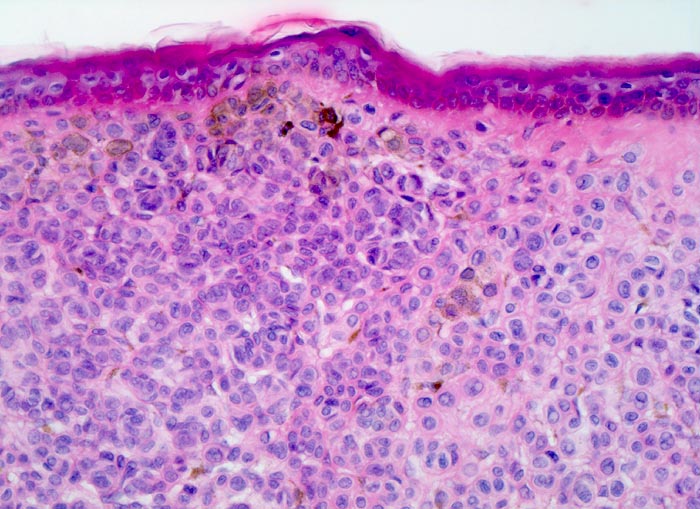

PathoPic – image database / PathoPic ID 3577 - dermaler Naevuszellnaevus

dermaler Naevuszellnaevus

benigner Tumor

Haut, Rumpf

Dünne Epidermis ohne Infiltrate von Naevuszellen. Die Naevuszellen im Corium bilden dichtliegende Zellballen. Vor allem in den oberflächlichen Naevuszellen lässt sich braunes Melaninpigment nachweisen.

Graubraune, leicht erhabene, scharf begrenzte Hautveränderung über dem Schulterblatt.

Histologie

200